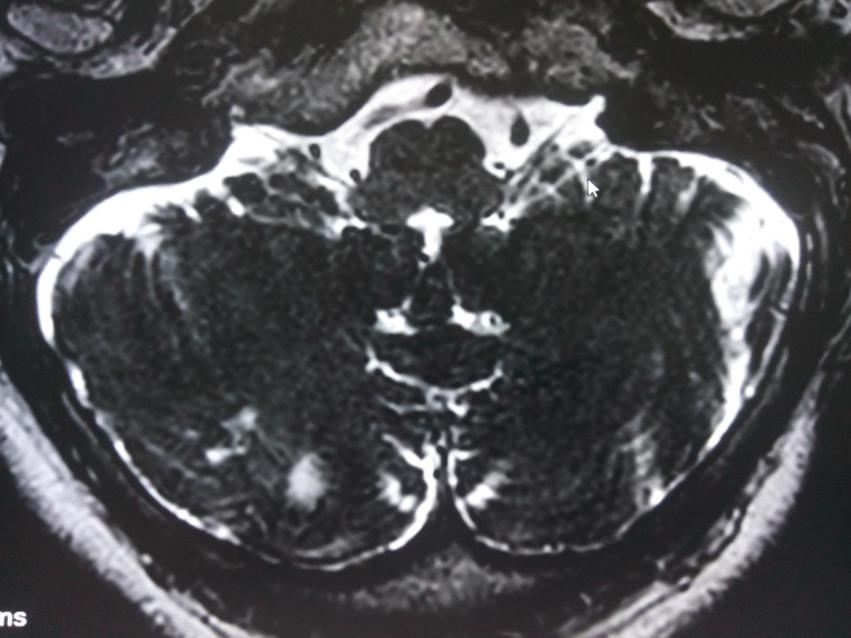

半球脑软化继发癫痫案例

患者张某,女性,11岁(入院时年龄) 患者出生70天时无明显诱因下出现一次肢体抽搐,身体倾倒,头偏一侧,伴意识丧失,持续约2-3分钟后自行缓解。3天后出现双眼上视,愣神,持续约1分钟,缓解,未于抗癫痫治...【详细】